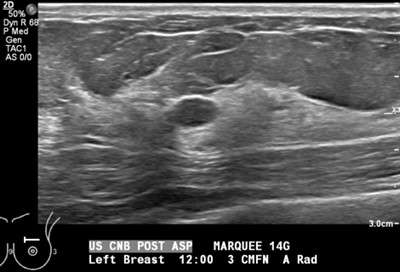

• Technologist saves a final image to document that the cyst has decreased in size and/or completely collapsed (Figure 3).

Procedure: US Guided Cyst Aspiration Figure 3

Figure 3. Post-aspiration grayscale sonogram shows complete collapse of the more posterior cystic structure, indicating that the internal contents have been successfully aspirated.